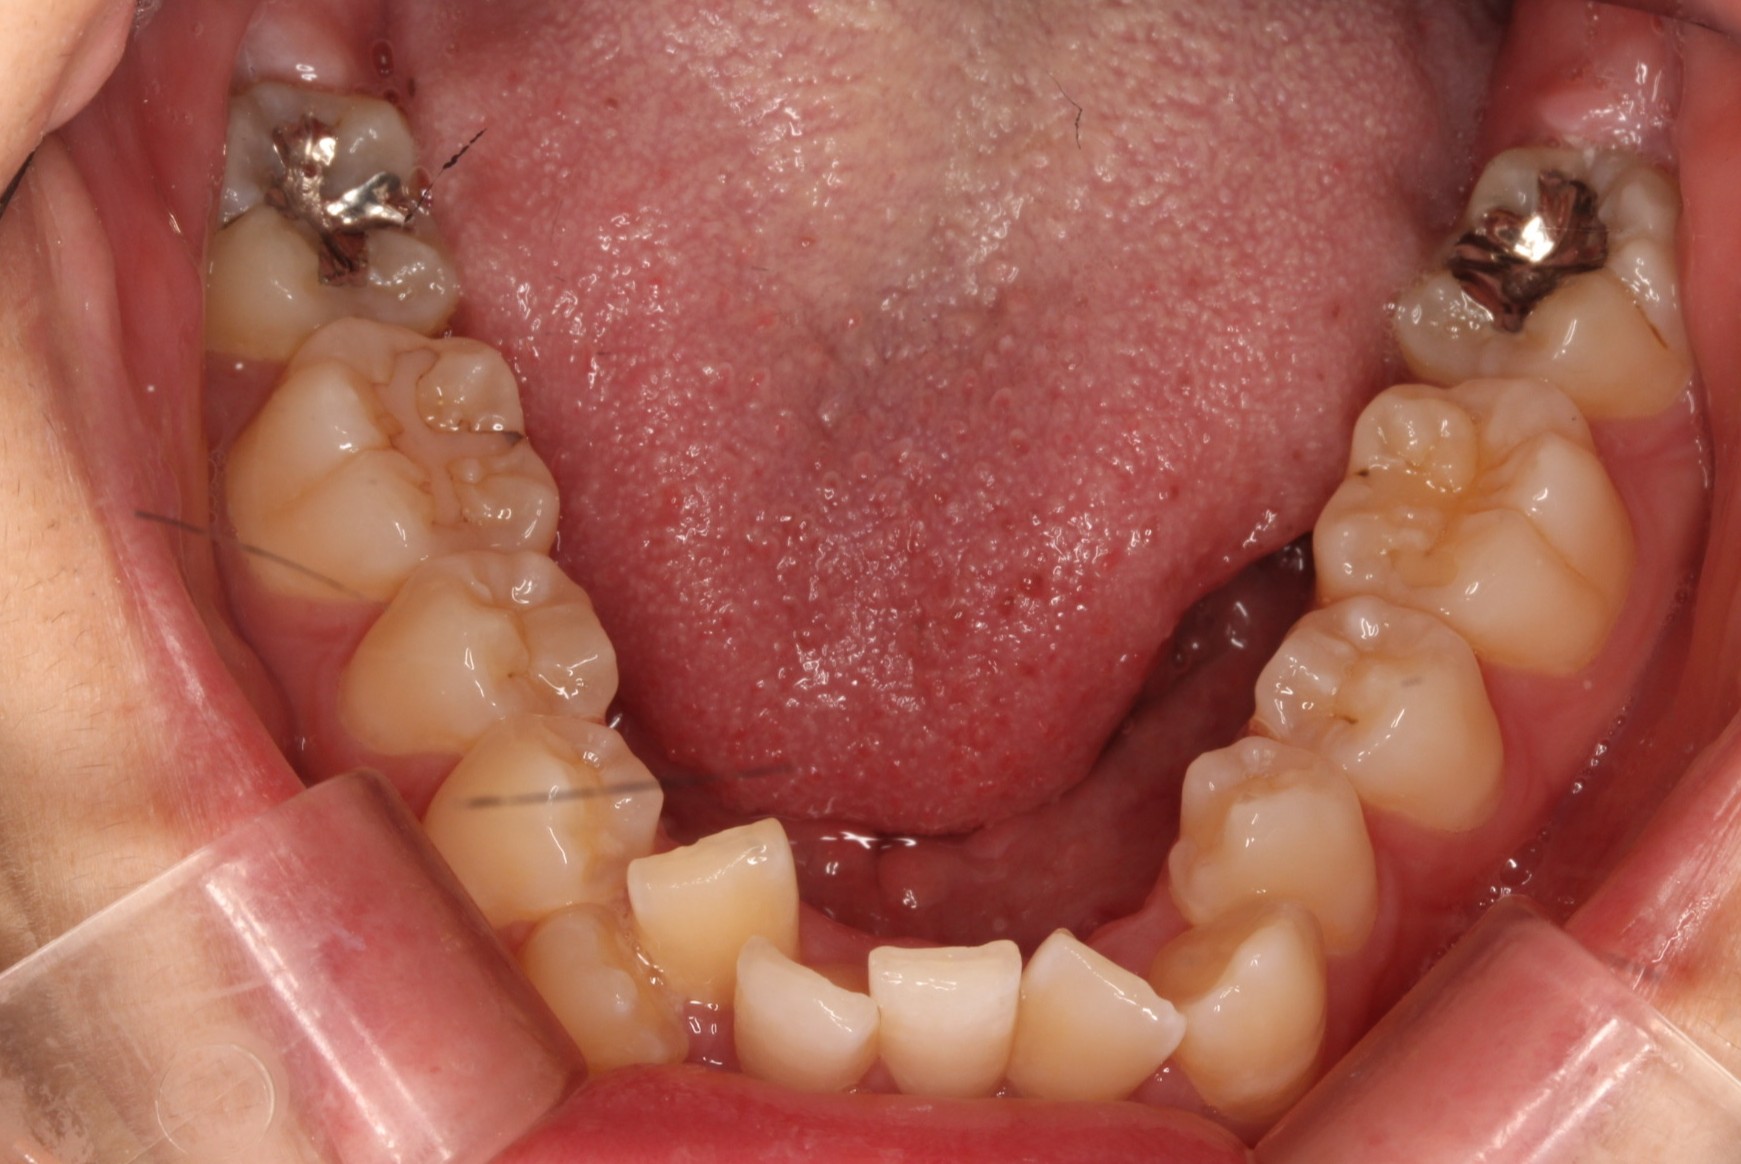

矯正術前:上顎

矯正術前:下顎